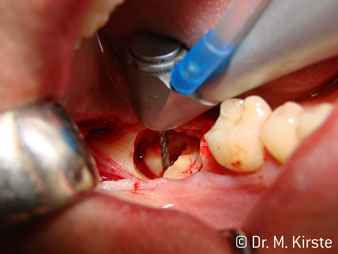

La scelta dell'angolo di 45° del contrangolo offre numerosi vantaggi in sede di utilizzo. I colleghi chirurghi, per i quali è stato messo a punto in primo luogo il contrangolo, noteranno in fretta la possibilità di lavorare in modo molto mirato. In particolare, durante l'estrazione dei denti del giudizio (Fig. 2), non sono necessarie estese resezioni del tessuto molle nell'area della guancia (Fig. 3). La forma della testina del contrangolo, insieme a lievi rotazioni della stessa durante la preparazione, permettono di lavorare in modo rapido e sicuro nella regione retromolare.

La concezione professionale del sistema di cuscinetti nel cuore della testina del contrangolo assicura un funzionamento silenzioso delle frese; durante l'estrazione di denti e radici (Fig. 4 - 9) si ottiene un taglio estremamente preciso e stabile.